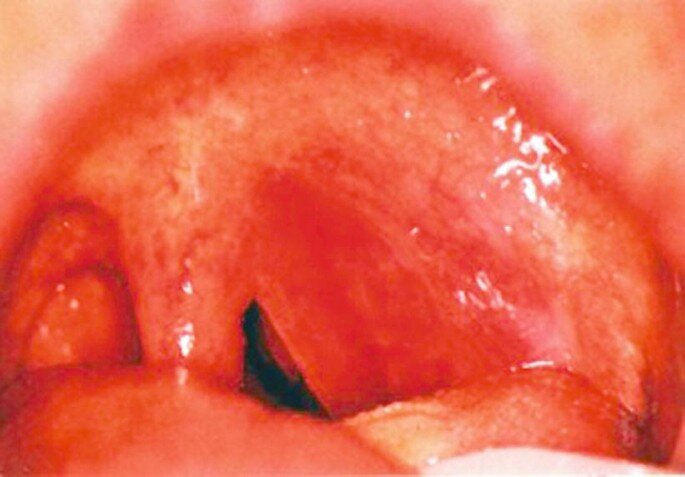

Диагноз я заподозрила с порога, когда ребенок с трудом произнес свое имя, как-будто, во рту что-то есть. При осмотре рта, был настолько яркая и типичная картина, что других вариантов для диагноза не было. Ярко-красное смещенное в одну сторону мягкое небо и выпирающая миндалина. Если вы хотя бы один раз в жизни видели такого пациента, вряд ли ошибетесь во второй раз с диагнозом.

Это паратонзиллярный (перитонзиллярный) абсцесс (ПТА)